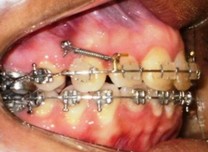

Ortodoncia con micro implantes

Tratamientos de ortodoncia

combinados con la instalación de

microimplantes como refuerzo mecánico.